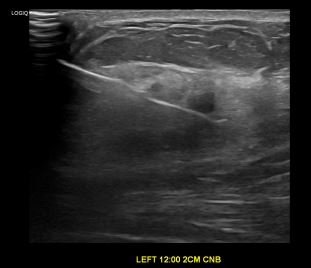

상기환자는 만져지는 멍울로  내원하신 40대후반

여성분으로 의심스러운 좌측혹 조직검사 시행해 침윤성암 으로 진단되었습니다